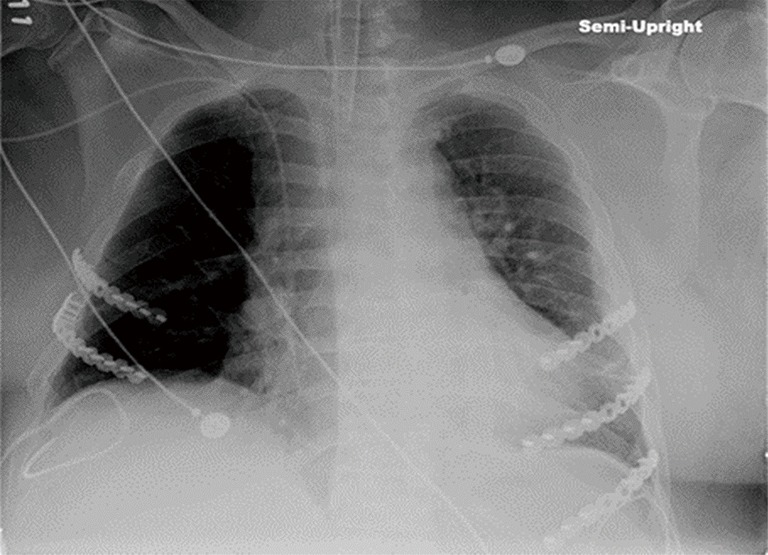

Figure 4.

Chest X-ray after the second round of cardiopulmonary resuscitation illustrating no additional rib fractures, intact plates, and absence of screw pullout.